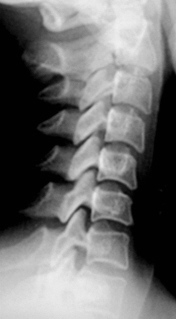

Иллюстрации 5, 6, 7. Определяется выраженная «сглаженность» шейного лордоза на уровне С2-С6. Определяется некоторая скошенность передне-верхних лимбусов тел С4, С5. В положении разгибания определяется смещение кзади тел С3, С4, С5 в виде лестничной комбинации, что свидетельствует о нестабильности в сегментах С3-С4, С4-С5, С5-С6 и указывает на дистрофические изменения в межпозвонковых дисках указанных сегментов.

Иллюстрация 7 – фрагмент с увеличением, на котором четко определяется смещение кзади тел позвонков.